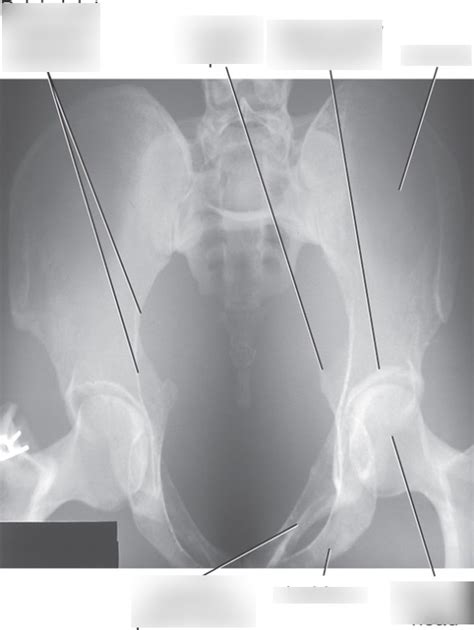

Image Evaluation and Anatomy

Okay, you’ve taken the X-ray – now what? Evaluating the image is just as important as taking it. You need to know what you’re looking at and what constitutes a good image. The key to image evaluation is systematic assessment. Start by checking the image for proper positioning, collimation, and exposure. Is the pelvis straight? Is the entire area of interest included? Is the image too dark or too light?

Key Anatomical Structures to Identify:

• Sacroiliac (SI) Joints: These joints connect the sacrum to the iliac bones. On the AP Axial view, you should be able to clearly visualize the SI joints and assess their alignment and joint space.

• Symphysis Pubis: This is the joint where the two pubic bones meet in the front of the pelvis. Look for any widening or displacement of the symphysis pubis, which could indicate a pelvic fracture or instability.

• Pelvic Inlet: This is the opening into the true pelvis. The AP Axial view is designed to provide a clear view of the pelvic inlet, allowing you to assess its shape and symmetry. Any distortion or asymmetry could suggest a fracture or dislocation.

• Iliac Crests, Ischial Spines, and Pubic Rami: These bony landmarks should be clearly visible and free from any obvious fractures or deformities.

• Sacrum and Coccyx: Although the primary focus is on the pelvic ring, it’s also important to assess the sacrum and coccyx for any abnormalities.

• Rotation: Check for rotation by assessing the symmetry of the obturator foramina and the iliac wings. If one obturator foramen appears larger than the other, or if one iliac wing is more prominent, the pelvis is likely rotated.

• Collimation: Ensure that the collimation includes the entire pelvis, from the iliac crests to the proximal femurs. Cutting off any of these structures could result in a missed diagnosis.

• Exposure: The image should have adequate density and contrast to clearly visualize the bony structures of the pelvis. Overexposure (too dark) can obscure subtle fractures, while underexposure (too light) can make it difficult to assess the soft tissues.